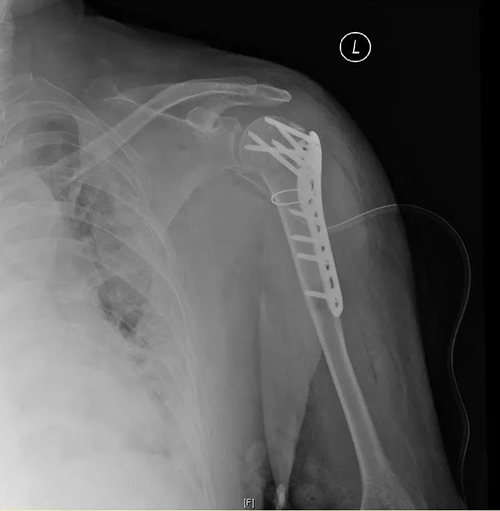

胸外科王磊主任医师经前胸第三肋间开胸,探查发现肱骨头位于左肺上叶深部,并导致肺部裂伤,徒手取出肱骨头后,对裂伤的肺叶进行了修复,放置胸腔闭式引流。肱骨头取出后,张琰主任医师对严重粉碎的复杂肱骨近端骨折进行了准确的解剖复位及可靠的内固定。手术历时约3小时,术中患者生命体征平稳,术后患者安返病房,病情稳定,术后第四天顺利拔除胸腔闭式引流,恢复良好,顺利出院。

术后平片,骨折解剖复位